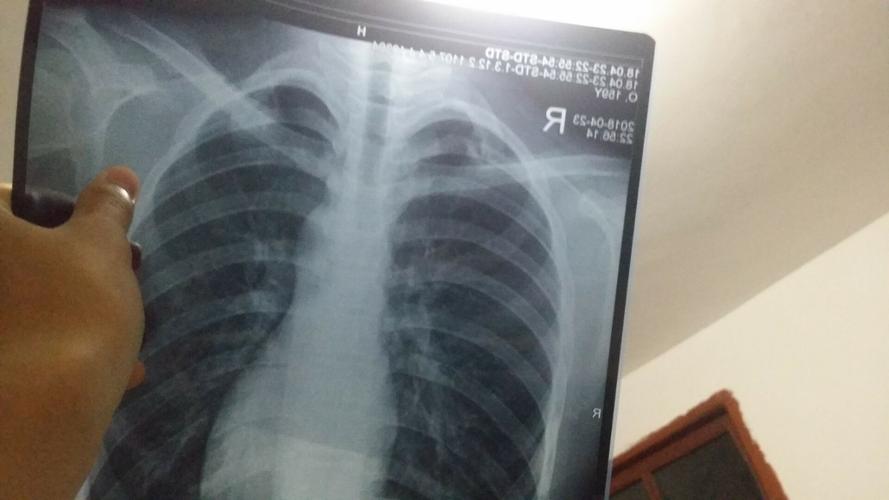

医院拍了几张胸片,肺部有什么症状吗